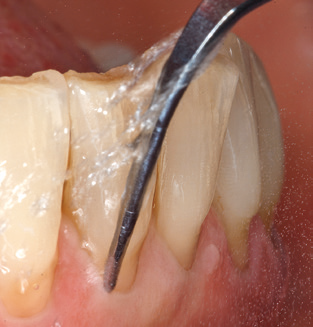

Una buona illuminazione del campo di lavoro facilita notevolmente il processo. Il sistema utilizzato dagli autori ottiene questo risultato grazie a un anello LED 5x integrato nel manipolo. Naturalmente, viene offerta anche una serie di consigli di lavoro per diverse indicazioni. Un inserto diritto, utilizzabile universalmente, è lo strumento di base necessario per la pulizia meccanica dei denti naturali (Fig. 5a e b). Sono disponibili anche inserti curvi, che consentono l'accesso alle forcazioni esposte, per le aree difficili da raggiungere nella regione posteriore (Fig. 6).